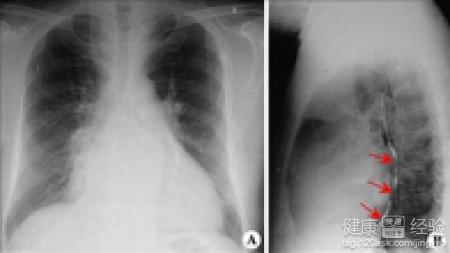

心肌病就是心尖肥大有什麼辦法治嗎

1心肌病我們剛開始的時候並不是很在意它,起初也沒有什麼特別的症狀,後來慢慢就會出現自己的胸口疼痛還有的時候我們會感到自己的呼吸困難,有的時候走一會路我們就覺得自己的呼吸更加困難。

2記得我們有前陣子忽然感到自己的胸口疼痛,後來去醫院才知道自己得了心肌病後來開了黃芪30克、太子參20克、麥冬15克、柴胡15克、白芍12克、丹參10克,等服用了幾天症狀明顯比之前好多了。

3得了心肌病我們平常的時候要按時休息,不要經常熬夜,飲食也要保持清淡,不要吃一些辛辣刺激的食物,不要和一些咖啡的飲料,要適當的參加體育鍛煉,不要過度的運動,要保持一顆樂觀的心態。